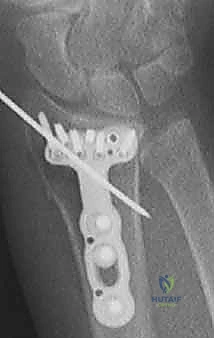

ثانياً: العلاج الجراحي (Surgical Intervention)

متى يقرر الدكتور هطيف ضرورة التدخل الجراحي؟

1. عدم الاستقرار (Instability): إذا كان المفصل الزندي الكعبري البعيد (DRUJ) غير مستقر بعد تثبيت كسر الكعبرة.

2. الانزياح (Displacement): إذا كان الكسر في قاعدة الناتئ الإبري منزاحًا بأكثر من 2 ملم.

3. الكسور المفصلية: أي كسر يخل بتطابق السطح المفصلي لرأس الزند.

4. الكسور المفتتة: في الجزء الكردوسي التي تؤدي إلى قصر عظم الزند.

5. الكسور المفتوحة (Open Fractures): حيث يبرز العظم من الجلد، وتتطلب جراحة طارئة لتنظيف الجرح وتثبيت الكسر لمنع العدوى.

خطوات التدخل الجراحي الدقيق مع الأستاذ الدكتور محمد هطيف

تُعد جراحات المعصم والزند من الجراحات الدقيقة التي تتطلب مهارة عالية، وهو المجال الذي يتفوق فيه الأستاذ الدكتور محمد هطيف بفضل استخدامه لتقنيات الجراحة المجهرية (Microsurgery) والأدوات الجراحية ذات التقنية العالية.

1. التخطيط ما قبل الجراحة (Pre-operative Planning)

يقوم الدكتور هطيف بدراسة الأشعة المقطعية ثلاثية الأبعاد بدقة، ويختار نوع وحجم الصفائح المعدنية (Plates) والمسامير (Screws) المناسبة لكل مريض بناءً على حجم العظم ونوع الكسر.